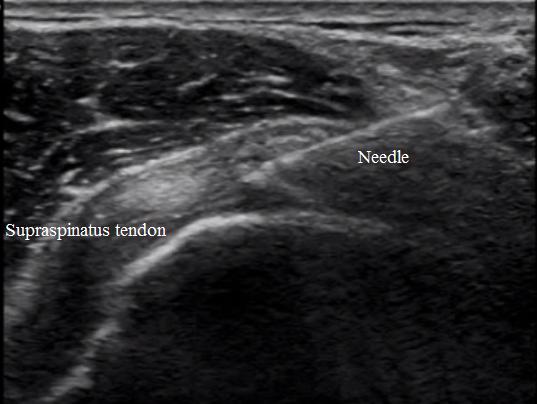

Diagnostyka USG - Iniekcja do barku z widoczną igłą

Iniekcja do barku z widoczną igłą - precyzja dzięki USG.

Jedynie dzięki wsparciu USG można wykonać dokładne nakłucie lub podanie leku w określoną, chorą okolicę ciała. Ultrasonografia jest nieinwazyjną, w pełni bezpieczną techniką obrazowania tkanek miękkich, na świecie powszechnie wykorzystywaną w diagnostyce i zabiegach miniinwazyjnych. Niedokładne podanie leku lub wykonanie punkcji może spowodować m.in. uszkodzenie naczynia krwionośnego lub być przyczyną braku efektu terapeutycznego.

Sonochirurgia barku - precyzyjne nakłucie zwapnień pod kontrolą USG, np. ścięgien pierścienia rotatorów z ewentualnym wypłukaniem zwapnień, iniekcje do kaletki podnaramienno-podbarkowej z leku (blokady), iniekcje dostawowe, ostrzykiwanie uszkodzonych struktur osoczem bogatopłytkowym z czynnikami wzrostu lub Orthokine.